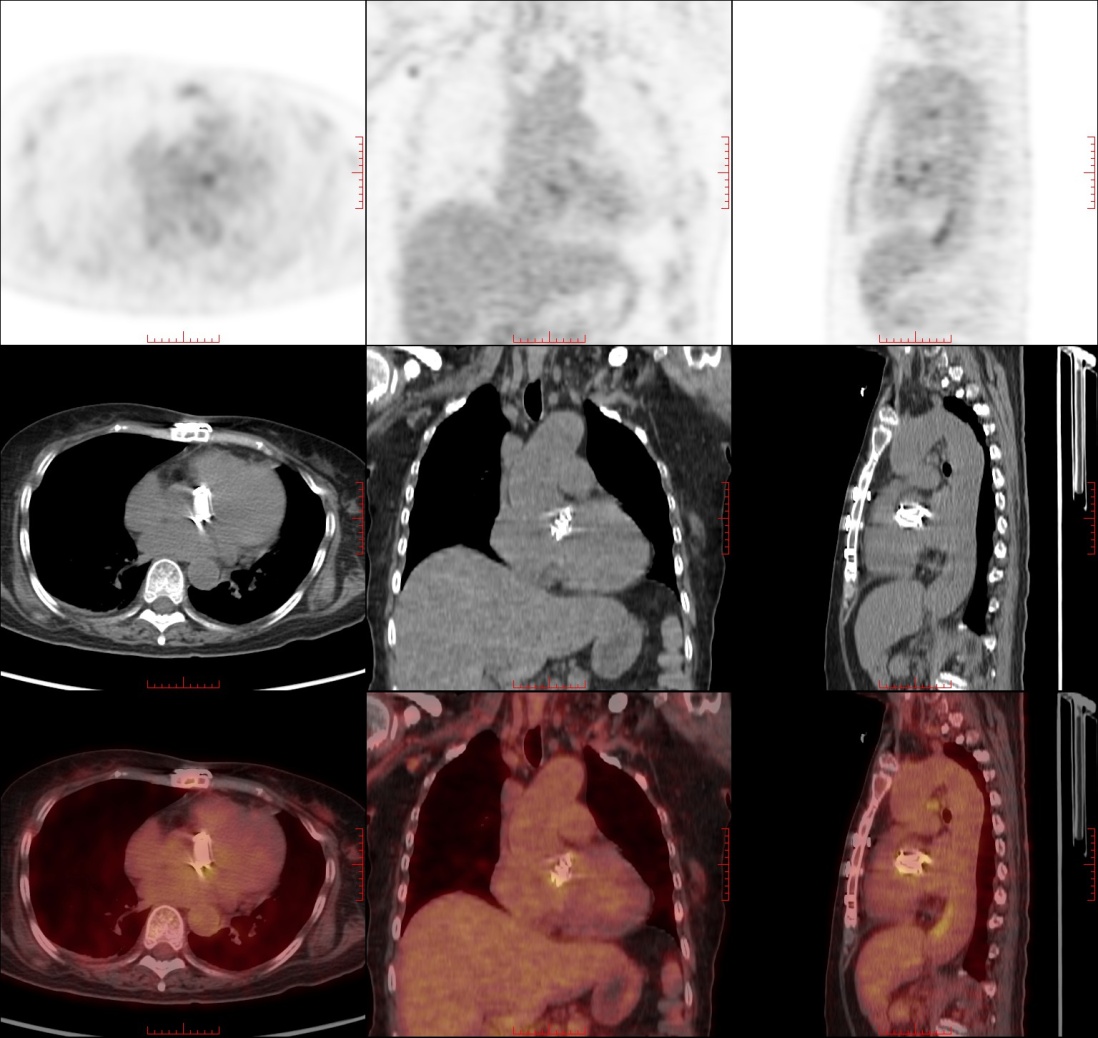

转入感染科之后的诊断及治疗过程:入科后继续予头孢他啶阿维巴坦(2.5 g/次,1次/8h)、替加环素(50 mg/次,1次/12h)及氨曲南(2 g/次,1次/q8h)静脉滴注抗感染,炎症指标继续下降,因患者有人工瓣膜植入术史、ICU住院史及两次骨科侵入性手术经历,痰及血培养为CRKP,除败血症外需警惕人工瓣膜感染性心内膜炎,住院期间多次经胸超声心动图检查均未见明显异常,因患者畏惧有创性经食管超声心动图,最终采用灵敏度更高的无创PET-CT检查得以确诊,11月15日完善全身PET-CT提示人工瓣膜周围小斑片状FDG高代谢,炎症可能,请结合临床(图1)。根据DUKE标准,患者被诊断为“感染性心内膜炎”遂给予足疗程抗生素治疗(≥6周)。足疗程抗感染治疗后患者炎症指标降至正常,症状及指标稳定后于2022年12月22日出院。

Figure 1. The patient’s PET-CT findings revealed patchy FDG-avid lesions surrounding the prosthetic valve

1. 患者PET-CT表现:人工瓣膜周围小斑片状FDG高代谢

早期PVE是指瓣膜置换术后1年内发生的感染,本案例于人工心脏瓣膜置换后7个月发病,符合早期PVE诊断。PVE的诊断较为困难,其临床表现常与术后感染性发热重叠,且其传统诊断基石经胸超声心动图(Transthoracic Echocardiography, TTE)与经食管超声心动图(Transesophageal Echocardiography, TEE)的诊断性能受限。综述指出,TTE对自体瓣膜心内膜炎赘生物的检出敏感性约为65%,而TEE虽可提升至90%~100%,但在存在人工瓣膜或心脏植入式电子设备时,二者仍可能对高达30%的IE病例得出阴性或不明确的结论[9]。人工瓣膜产生的声影伪影,是导致微小赘生物和瓣周并发症难以被准确检出的主要原因[10]。为解决超声心动图诊断PVE的局限性,功能代谢成像技术18F-FDG PET/CT日益凸显其价值,其诊断敏感性为73%至100%,能有效区分早期PVE与术后感染,在血培养阴性或超声心动图结果不明确时更具优势。PET-CT通过18F-FDG代谢摄取差异辅助鉴别感染与术后无菌性炎症,其可靠性源于直接显示感染相关代谢活性,且其诊断不依赖解剖结构变形,能有效克服人工材料伪影,实现早期诊断和全身评估[9]。在PET-CT影像中PVE病灶通常表现为局灶性、非均匀的FDG高代谢,而未感染的瓣膜中观察到的FDG摄取通常是弥漫且均匀的轻中度代谢,最新的文献数据表明,心脏瓣膜置换术后3个月内的术后反应性炎症相关代谢活动不影响PET-CT对早期PVE的诊断[11]。本病例发病后曾多次行超声心动图检查但无阳性结果,最终通过PET-CT确诊,印证了该技术在PVE诊断中的核心价值。因此,对于临床高度怀疑PVE但超声阴性的病例,应优先采用PET-CT等新型影像技术以提高诊断效能。